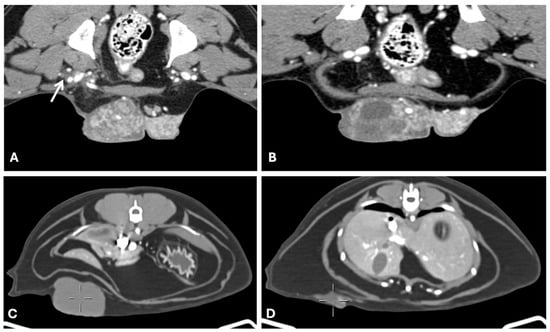

4.2. Computed Tomography

- Soultani, C.; Patsikas, M.N.; Mayer, M.; Kazakos, G.M.; Theodoridis, T.D.; Vignoli, M.; Ilia, T.S.M.; Karagiannopoulou, M.; Ilia, G.M.; Tragoulia, I.; et al. Contrast Enhanced Computed Tomography Assessment of Superficial Inguinal Lymph Node Metastasis in Canine Mammary Gland Tumors. Vet. Radiol. Ultrasound 2021, 62, 557–567. [Google Scholar] [CrossRef]

- Soultani, C.; Patsikas, M.N.; Karayannopoulou, M.; Jakovljevic, S.; Chryssogonidis, I.; Papazoglou, L.; Papaioannou, N.; Papadopoulou, P.; Pavlidou, K.; Ilia, G.M.; et al. Assessment of Sentinel Lymph Node Metastasis in Canine Mammary Gland Tumors Using Computed Tomographic Indirect Lymphography. Vet. Radiol. Ultrasound 2017, 58, 186–196. [Google Scholar] [CrossRef] [PubMed]